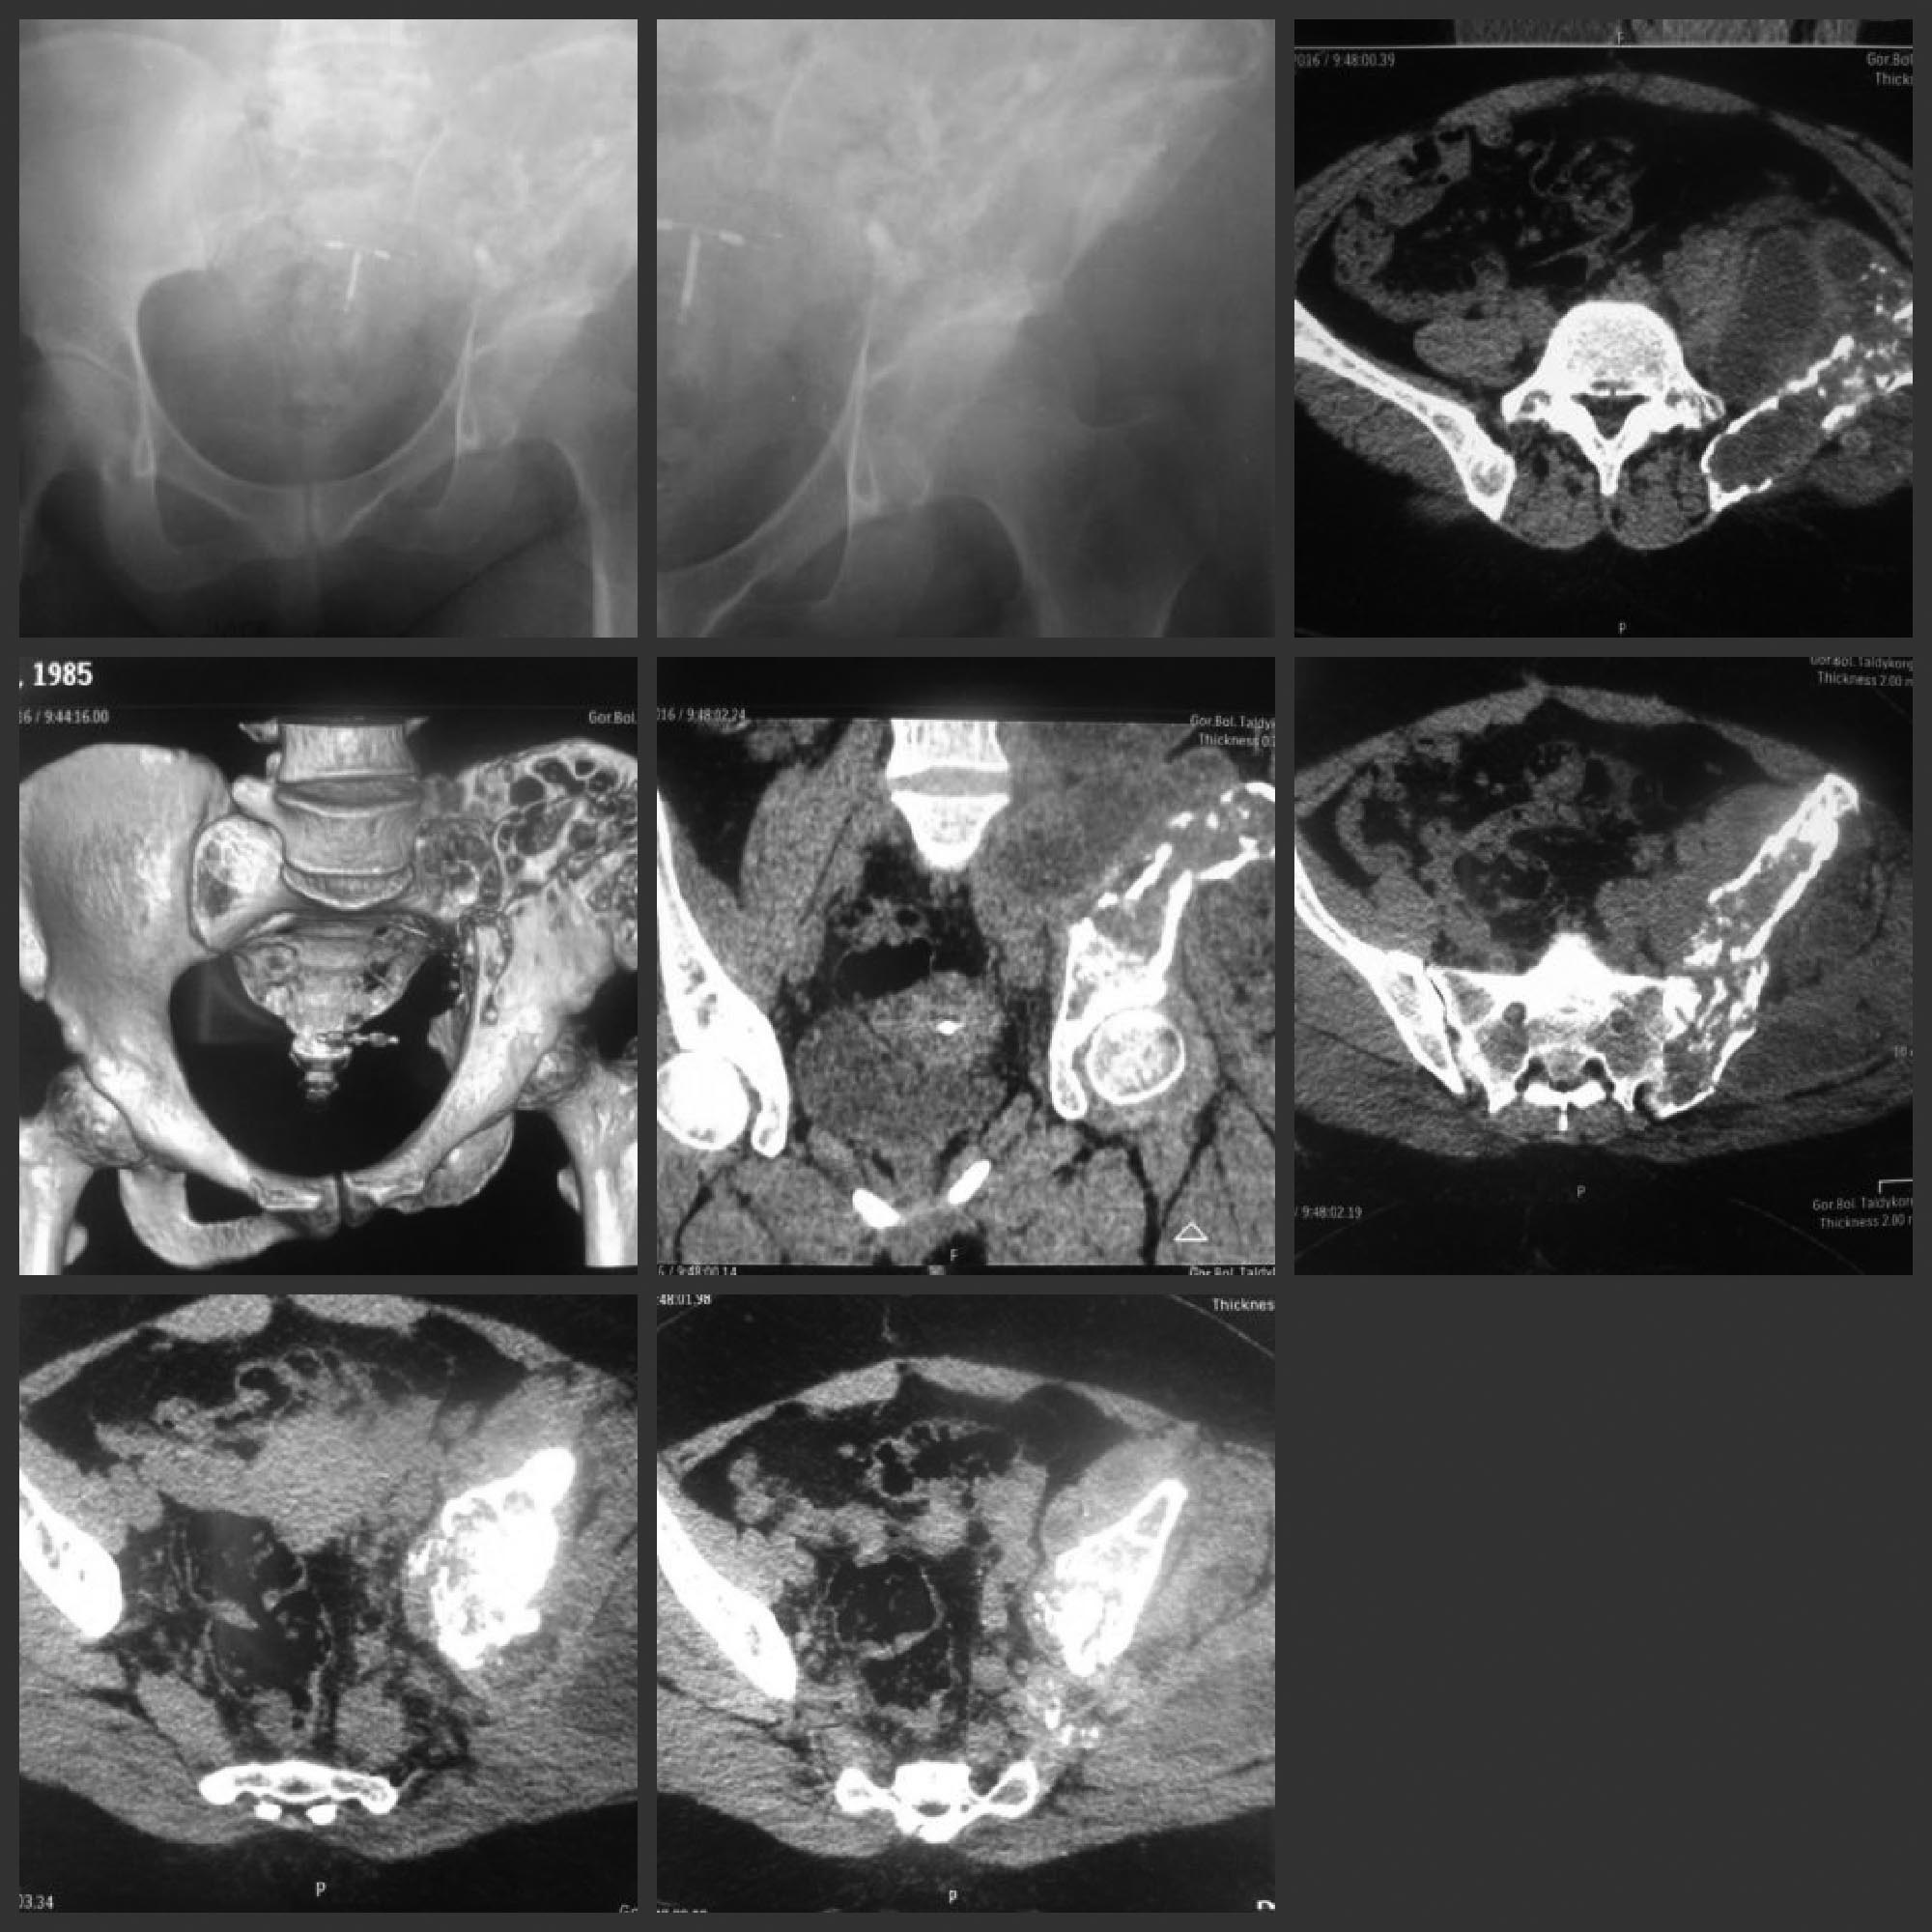

Здравствуйте. Нужна помощь в лечении эхинококкоза костей таза, 5 поясничного позвонка, левого бедра.

Больная 31 г. Жалуется на боли в области таза, хромоту.

Из анамнеза: Больным себя считает в течении 6 лет, когда появилась боль в поясничной и ягодичной областях. В 2013 году перенесла операцию по поводу эхинококкоза печени, забрюшинного пространства. В 2014 году иссекали эхинококковую кисту с прямой мышцы бедра слева. В данное время беспокоит боль в области таза слева.

Локально: при ходьбе пользуется тростью, хромает на левую ногу. При пальпации в поясничной, ягодичной областях, по передней поверхности левого бедра имеются плотные образования, не спаянные с подлежащими тканями; безболезненны.

Рентгенограмму и КТ-таза прилагаю.

Гистология: в препарате стенки кист, состоящие из хитиновых оболочек.

ИФА: IgG эхинококкоз положителен.